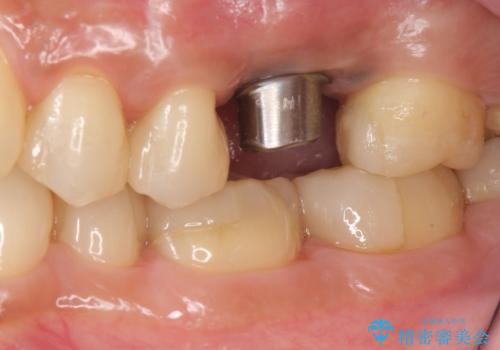

良い位置に良い方向でインプラントを埋入することができました。

手前の歯の虫歯もセラミックインレーで精度よく治療を行いました。